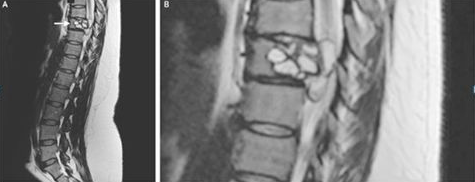

07 女子脊椎中发现寄生虫

一名法国妇女称其腿部会出现“电击”的感觉,经检查发现,她患有一种罕见的感染——脊椎里潜伏着绦虫幼虫。

这名女性背部的核磁共振显示,其脊柱有一处病变,需要手术切除。进一步的测试显示,这种病变是由细粒棘球绦虫感染引起的,这是一种小型绦虫,常见于狗和一些农场动物(绵羊、牛、山羊和猪等)。

这种绦虫可引起一种叫做包虫病的疾病,在这种疾病中,幼虫会形成囊肿,并在人体内缓慢生长。这种疾病在法国很少见,研究人员尚不清楚这位妇女是如何感染的。据报道,她曾接触过马和牛等农场动物。研究人员还怀疑,可能是吃了被寄生虫污染的蔬菜导致。在接受了一种抗寄生虫药9个月后,该妇女残留症状消失。

7月11日,《NEJM》杂志发表了该病例的报告。